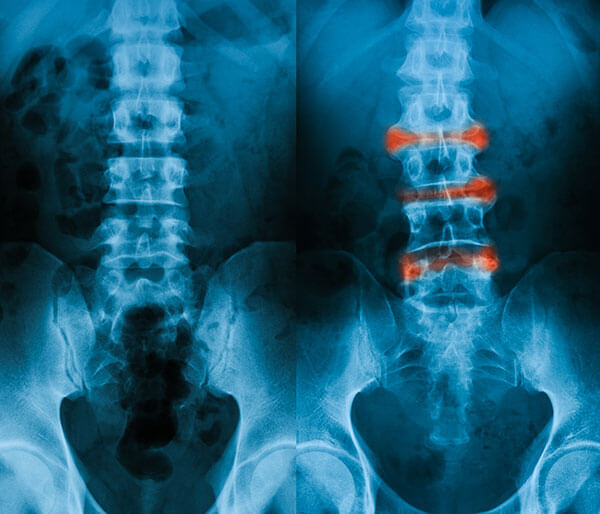

- Raze X: O radiografie permite medicului sa va vada articulatiile si oasele. El va cauta semne de fuzionare sau deteriorare.